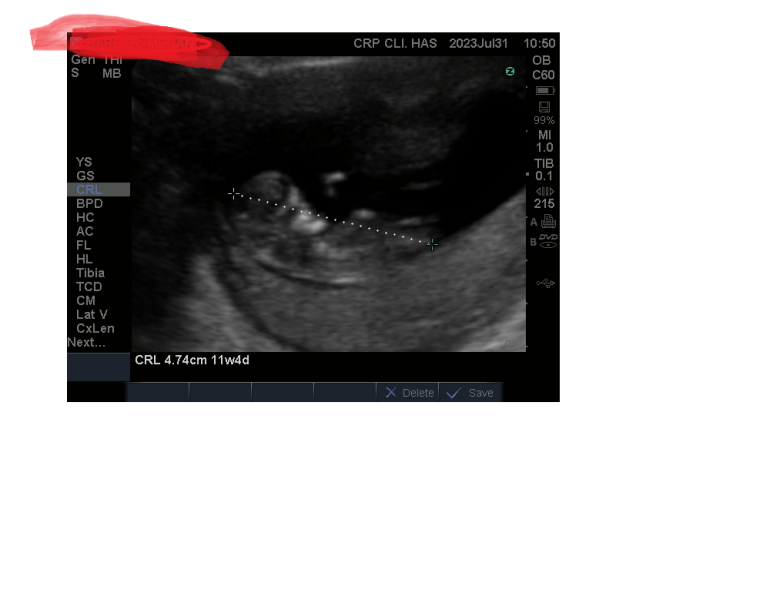

MeganBistram · 31/07/2023 13:05

Oh and its poor quality as its the portable scanner at Harley street, but here baby is today xx